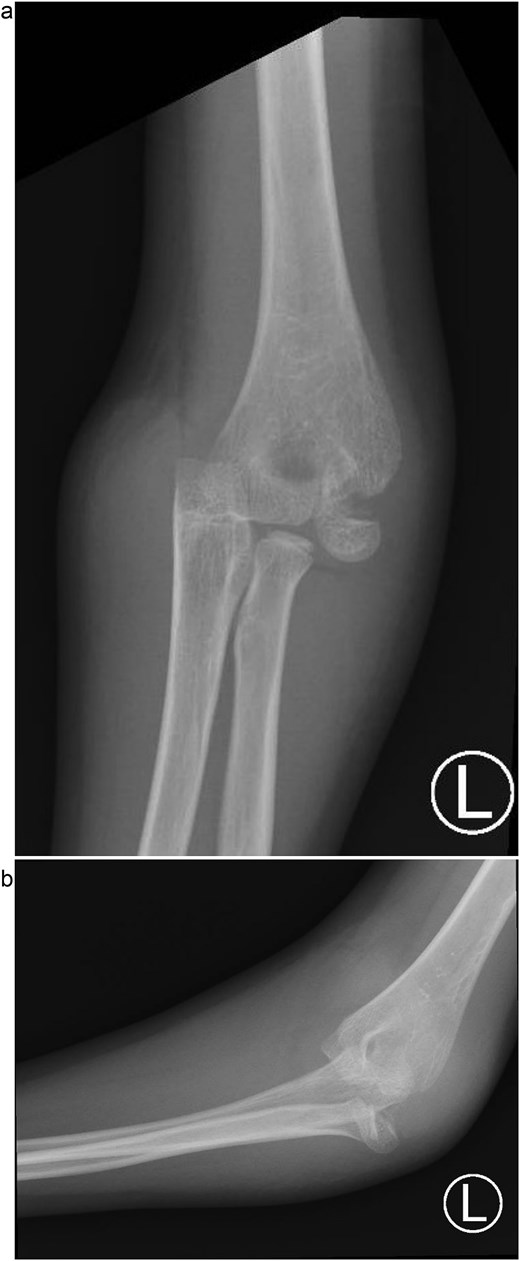

Under procedural sedation, closed reduction of the elbow dislocation was performed, restoring joint alignment and stability. However, post-reduction imaging showed persistent displacement of the lateral condyle fragment (Fig. 2a). The patient was subsequently taken to the operating room, where closed reduction of the condylar fracture was carried out under general anesthesia. As post-reduction displacement was less than 2–4 mm with intact articular cartilage, fixation was performed using two smooth Kirschner wires under fluoroscopic guidance. An arthrogram confirmed joint congruity and cartilage integrity (Fig. 3a). A long-arm posterior slab was applied with the elbow in <90° of flexion to minimize the risk of compartment syndrome (Fig. 4a).

(a) Immediate post-reduction anteroposterior radiograph showing restored joint alignment with persistent lateral condyle displacement. (b) Lateral view confirming maintained reduction of the ulnohumeral joint and residual separation of the lateral condyle fragment.